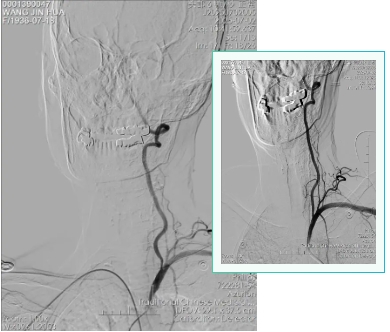

患者入院第2天,脑病科李成君主任带领介入团队为患者完善脑血管造影检查,结果示左侧椎动脉优势并起始处重度狭窄,狭窄率约80%,长度约8mm,结合颅脑磁共振枕叶梗死灶,考虑左侧椎动脉为此次卒中事件责任血管。与患者家属沟通病情、权衡获益与风险后,予经皮穿刺左侧椎动脉起始处重度狭窄球囊扩张并支架植入术,手术过程顺利。王大娘术后安返病房,继续抗板、降脂等急性脑梗死常规治疗,经积极治疗恢复良好,对治疗效果非常满意。